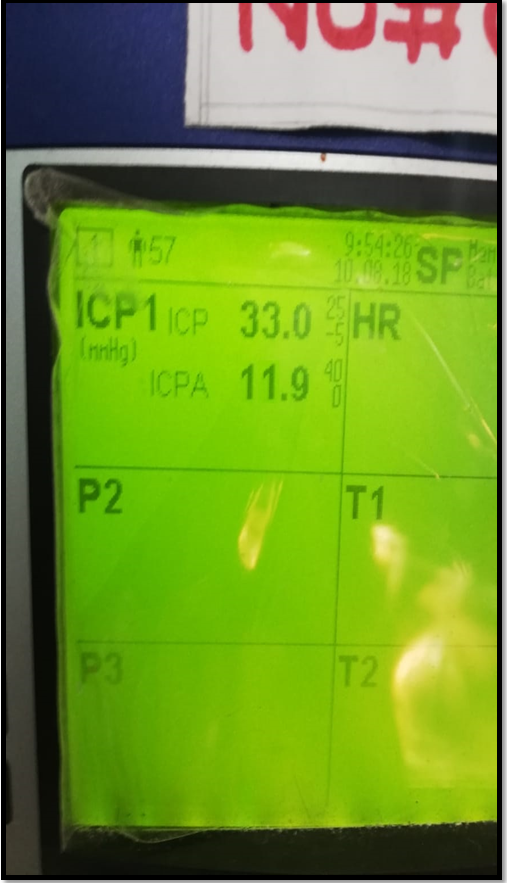

Repeat CT showed enlargement of frontal contusion. ICP was approaching to 37 and ICP A is 14 that is reflected the abnormal waveform.

Pre Operative Readings

P2 is taller than P1: Poor Compliance